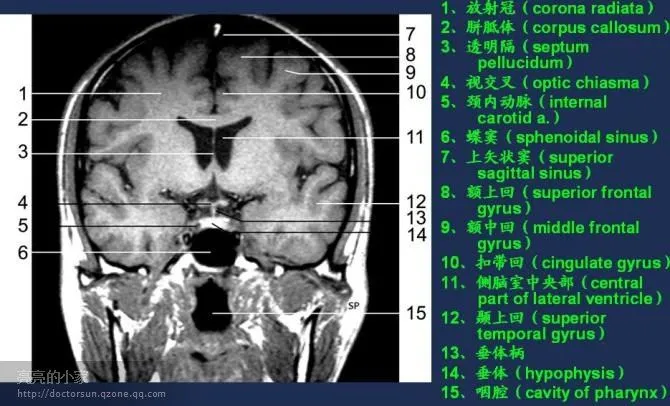

收藏!全身MRI解剖图谱,医生必备